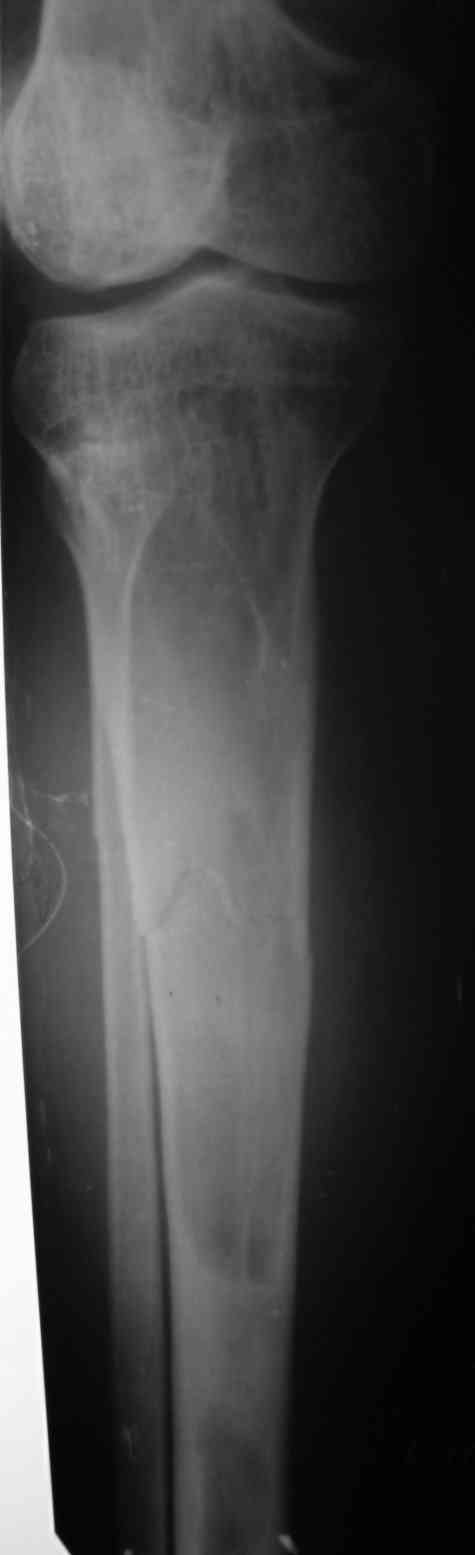

Re: Патологический перелом костей голени.

Вторая проекция.